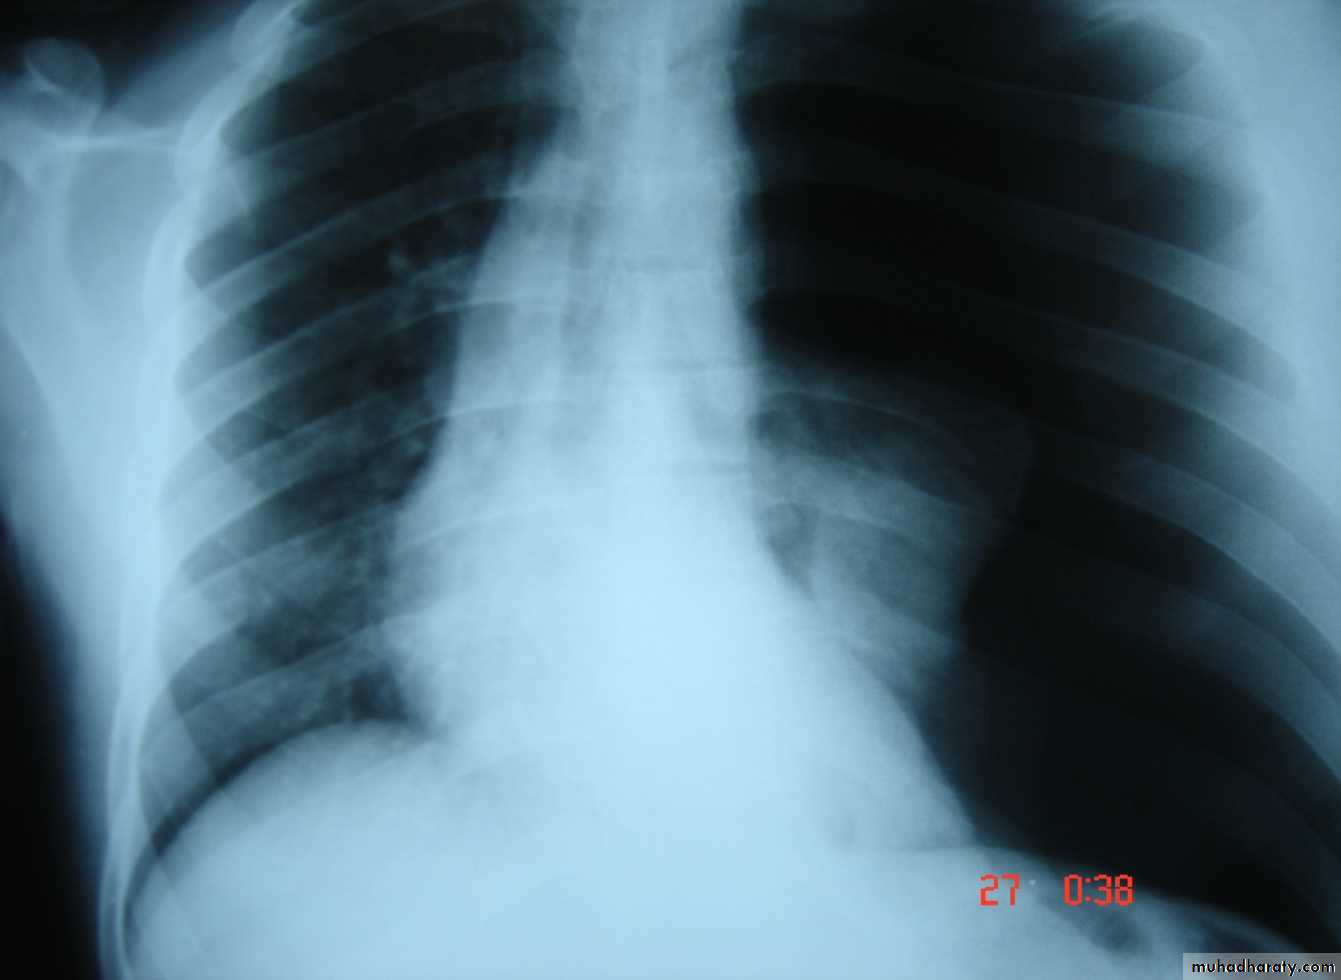

• 4-Pleural effusion

• Is the accumulation of fluid in the pleural space excessive transudation or exudation of the interstitial fluid from the pleural surface. It is signify pleural or systemic disease .

• Its effect depends on its size (mild , moderate or massive ) & the state of the underlying lung .It is classified as transudate when the protein content is less than 3g% or exudates when protein content is more than 3 gm % .Clinically patients will present with dyspnea & pleuritic chest pain

• Radio logically (concave meniscus sign)

• Transudate as in CHF

• Exudate as in malignancy